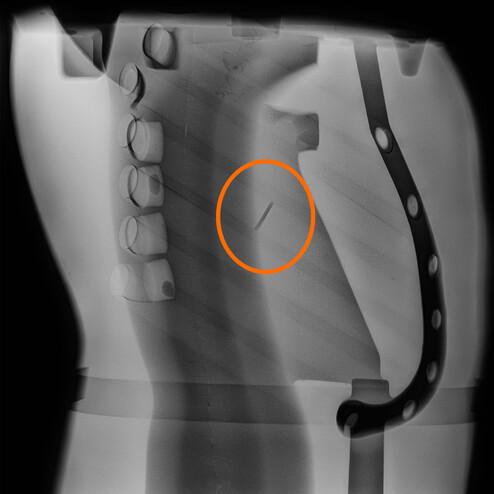

Bullet in protective vest

Rib fracture due to dynamically high load

Development of ballistic protective vests

Bullet through protective vest

Shot through ballistic protection plate

Shot channel in soft tissue of the dummy